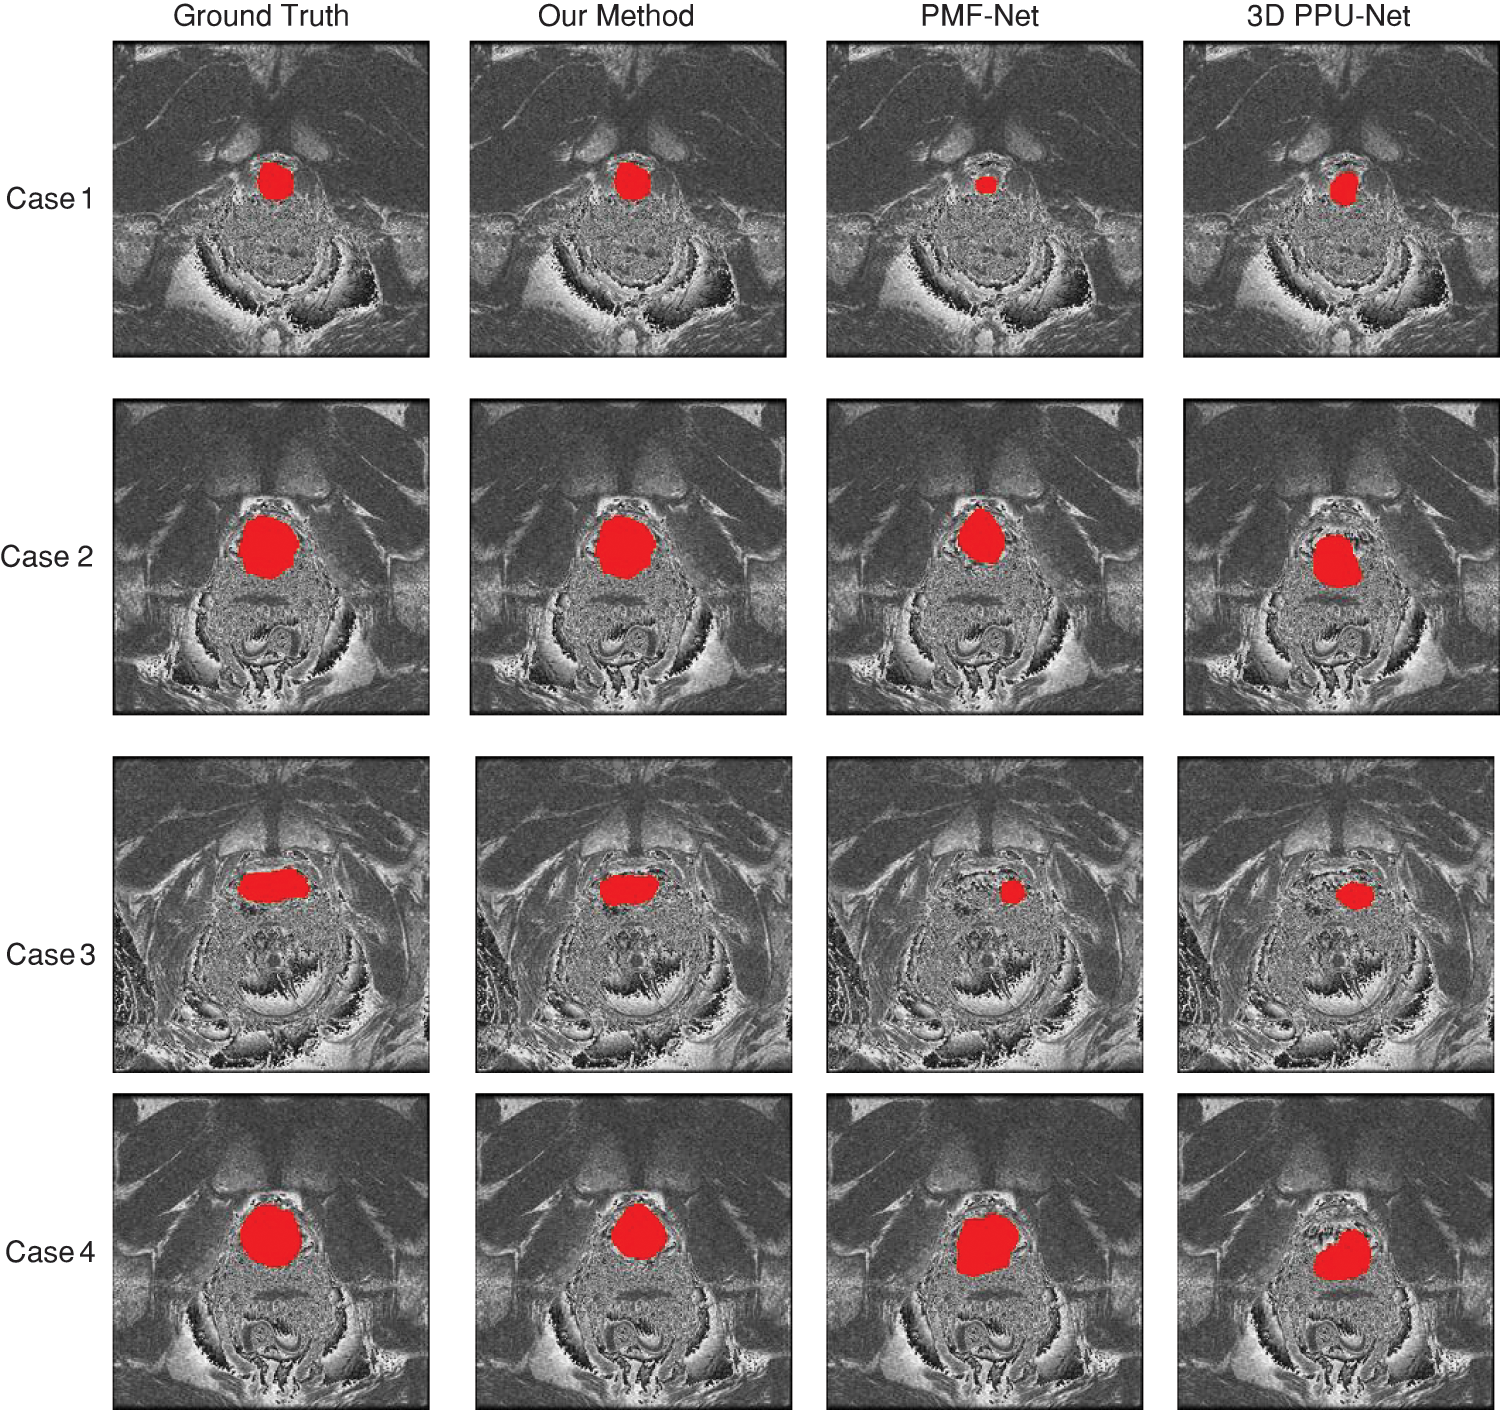

Using comparison approaches, the prostate region’s MRI image segmentation results are displayed in Fig. 9. Each column is the segmentation results of different methods: PMF-Net [8], 3D PPU-Net [9], and our method. As shown in Fig. 9, our method maintains higher consistency with the annotation than other methods. Our method has shown good segmentation results for smaller or blurry prostate regions. This depends on the multi-scale attention, transformer module, and feature fusion module we designed, which extract multi-scale information of the prostate and fuse global and local features, making the prostate segmentation results more accurate.

Figure 9: Comparison method for the prostate results of the MRI. Red denotes the prostate, which is a slice of the same case obtained using various techniques. Each column is the segmentation results of different methods: PMF-Net [8], 3D PPU-Net [9] and our method